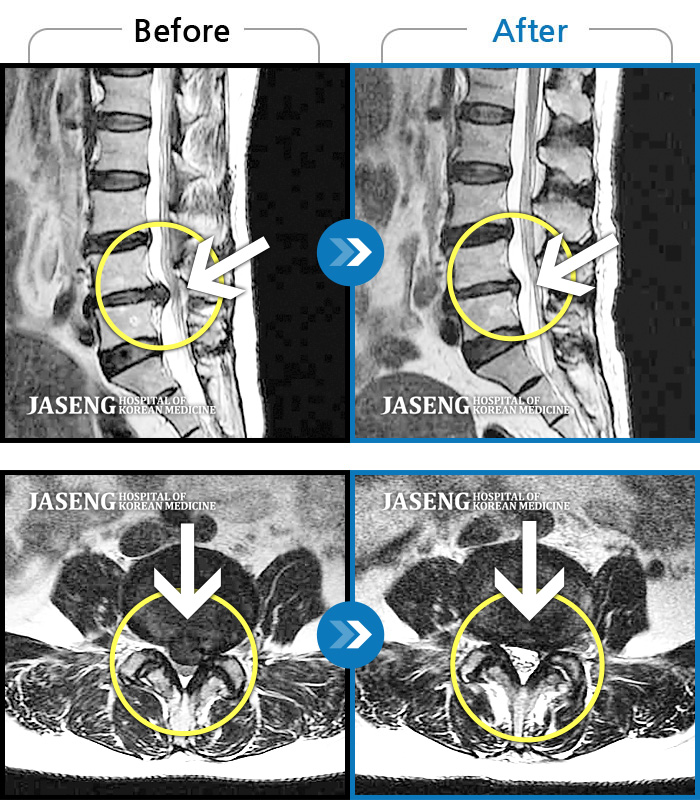

허리디스크

안산 · 김민수 원장

발목의 힘이 떨어져서 절뚝거리면서 걸었다.

촬영시기

2022.01.03 ~ 2024.07.31

2024.08.09